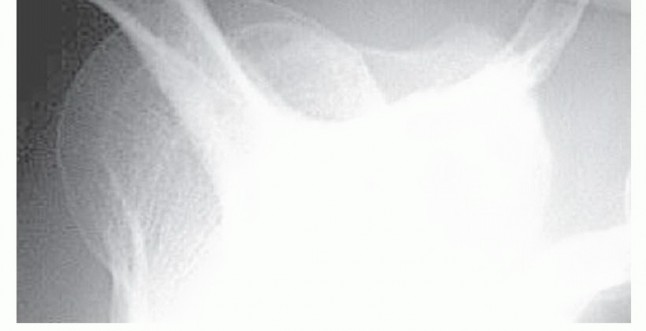

Standard anteroposterior (AP) radiographs in internal and external rotation and a supraspinatus outlet view should be taken for the evaluation of impingement syndrome. A supraspinatus or acromial outlet view is a transscapular view taken with the radiographic beam angled 15 to 20 degrees caudally(FIG 1). The outlet view is the best plain radiographic technique to evaluate acromial morphology and aid in detection of inferiorly directed enthesophytes. With this information, the surgeon may accurately plan the amount of osseous resection required to convert the acromion to type I morphology. Acromiohumeral distance is the minimal distance between the acromial undersurface and the humeral head. An acromiohumeral distance of less than 7 mm is considered abnormal. An abnormal acromiohumeral distance has been shown to correlate with the clinical status of patients. 18

### FIG 1 • Supraspinatus outlet view. This view helps the surgeon assess acromial morphology and facilitates preoperative planning for the amount of acromial resection. Additional views or diagnostic tests may be used to further evaluate the painful shoulder. Axillary lateral radiographs may be helpful in the diagnosis of os acromiale. Magnetic resonance imaging (MRI), computed tomography (CT) scan, arthrography, and ultrasonography should be reserved for patients whose diagnosis of impingement syndrome is not completely clear from the history, physical examination, and radiographs. These other modalities will also help diagnose biceps, labral, and rotator cuff pathology.